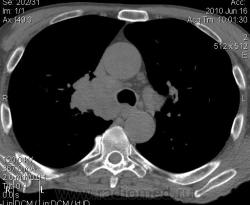

Мужчина 69 лет, с последствием ОНМК находился в доме-интернате для инвалидов. В анамнезе пневмония справа и исходом в пневмосклероз. ФЛГ не проходил 1.5 года. Анализы: СОЭ 20 мм/ч, остальное - без особенностей. Поступил в неврологическое отделение с диагнозом: повторное ОНМК. Невролог заподозрил метастазы головного мозга, направил на рентгенографию легких. После выявленых изменений в правом легком, пациент направлен на КТ головного мозга и грудной полости. От контрастирования и бронхоскопии категорически отказался.

По поводу подозрения на туберкулез пациента в прошлом нодократно проверяли, исключили. ФЛГ архива у меня нет. Все только со слов пациента. Кальцинаты в корне массивные. Трудно сказать, откуда опухоль (если это не конгломерат лимфоузлов!) плотностью 35 ед.Н - то ли из вехнедолевого бронха, который имеет культю 0.4 см и заканчивается выпуклым контуром, но при этом сохраняется воздушность почти всей доли; то ли периферический с центром в прикорневой зоне и вторичным прорастанием ВДБ. К сожалению забыла про снимок легких, на днях выставлю. Я первоначально считала периферический (верхушка, на фоне пневмосклероза) с мтс средостения. По плотности на верхушке узелок 5 ед.Н, только поэтому засомневалась, где же первичный. Лимфоузлы средостения множественные, до 2 см. Кроме того, на верхней стенке правого главного бронха есть мелкое образование такой же 35 е.Н плотности, то ли аденома, то ли прорастает... Без бронхоскопии - только гадать

это периферический рак S2 в/доли правого легкого с мтс во внутригрудные л/узлы.

А тут нечего гадать - данную демонстрацию можно поместить в учебник: узловое образование, с бугристыми, лучистыми контурами, связаное с плеврой, "дорожкой" к корню, перифокальной инфильтрацией. Корень расширен полицикличен за счет конгломерата увеличеных бронхопульмональных, трахеобронхиальных и бифуркационных л/узлов, значительно сдавливающих в/долевой бронх, с нарушением вентиляции в/доли.

Центральный рак ВДБ справа с мтс в л/узлы паратрахеальные нижние, верхние справа, БФ. МТС в головной мозг. А про печень мало сканов

Мне кажется в 6 сегменте печени мтс + еще мтс поражение левого надпочечника вероятнее всего. Мтс в нижние паратрахеальные (с обеих сторон)+бифуркационные л/у. Поражения верхних паратрахеальных не вижу (на коронарах), аксиалы - не показыны сканы выше верхнего края дуги аорты, так что я бы не говорил про поражение верхних медиастинальных лимфоузлов (хотя тут это уже не принципиально) + мтс в головной мозг. А так - центральный рак правого легкого.